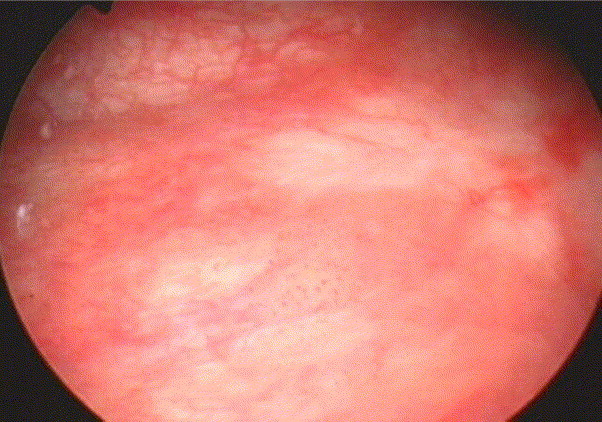

Mesane Kanseri Karsinoma in Situ (CİS)

Mesane kanseri karsinoma in situ (CİS), yüzeyde kabarıklık yapmayan yüksek dereceli üroteliyal karsinomdur. Biyopsi ile örneklenmediği takdirde enflamatuvar bir lezyon olarak yanlış tanımlanabilir veya gözden kaçabilir. CİS sıklıkla multifokal olup, mesane dışında üst üriner sistem, prostatik üretra ve prostatik kanallarda da bulunabilir. CİS, yüksek progresyon riski taşıyan bir histopatolojidir ve tedavi edilmezse, hastaların yaklaşık yarısında kas invazyonu gelişebilir.

- Yüzeysel Kabarıklık Yoktur: CİS, genellikle mesane yüzeyinde belirgin kabarıklıklara yol açmaz ve çoğu zaman biyopsiyle tespit edilir.